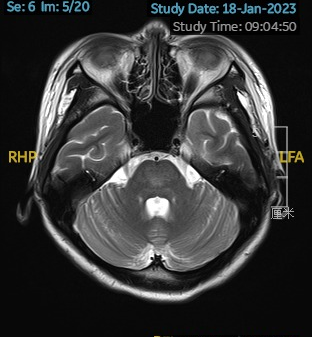

2023.01.18颅脑MR平扫示双侧基底节区及桥脑异常信号,考虑渗透性神经脱髓鞘综合征可能,见图1。

图1 2023.1.18颅脑MR成像示双侧基底节区及桥脑见对称性片样长T1长T2信号,FLAIR呈高信号。脑室、脑池、脑沟、脑裂未见明显异常。中线结构居中。小脑、脑干未见明显异常信号。